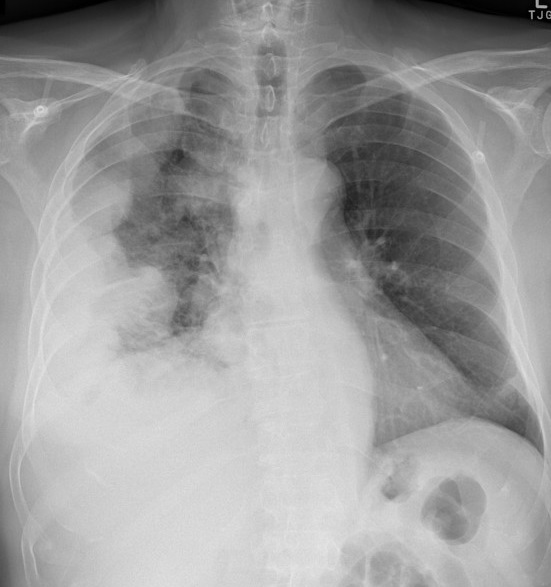

Image

calcification en plaque diffuse d'une ancien

tuberculose pleuro -pulmonaire droit . On peut en

vue encore de lesion ancienne tuberculeuse

fibrotique restrictive du poumon droit |